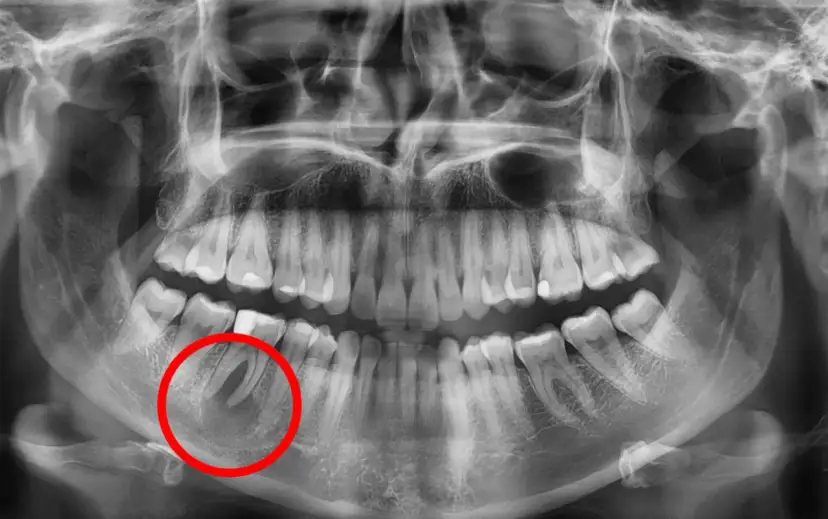

Zastanawiasz się, jakie są objawy torbieli zęba? Poznaj dyskretne i zaawansowane sygnały. Dowiedz się, dlaczego rośnie cicho i jak ją wyleczyć. Sprawdź!